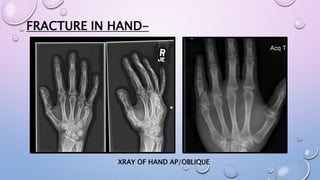

FRACTURE IN HAND-

XRAY OF HAND AP/OBLIQUE

FRACTURE IN HAND- XRAYOF HAND AP/OBLIQUE